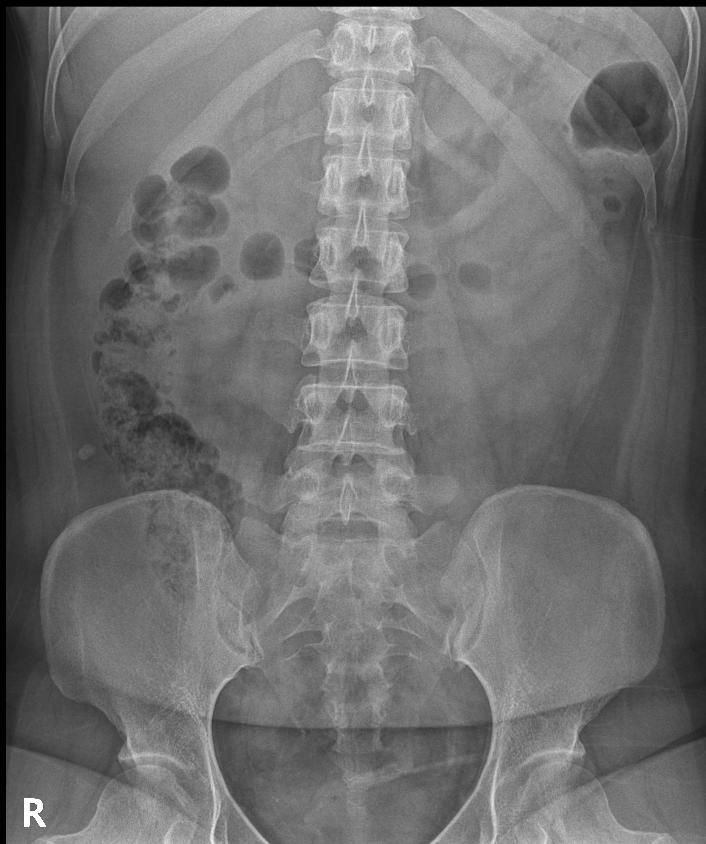

척추분리증인가요??(엑스레이 있어요)

한 병원에서는 척추분리증이라고 하고 한 병원에서는 척추분리증이 아니라고 해서요. 혹시 아래 사진에서 척추분리증 소견이 보이는 사진이 있나요??

여기까지가 a병원에서 찍은 사진이고 아래가 b병원에서 찍은 사진이에요!

• 2번 째 사진

A병원 세번째 사진의 아래 부위에 척추분리증이 있는게 맞습니다.

B병원 사진에서는 비교적 흐리게 보이지만 잘 보면 B병원 엑스레이에서도 같은 부위에 분리증을 확인할 수 있습니다.